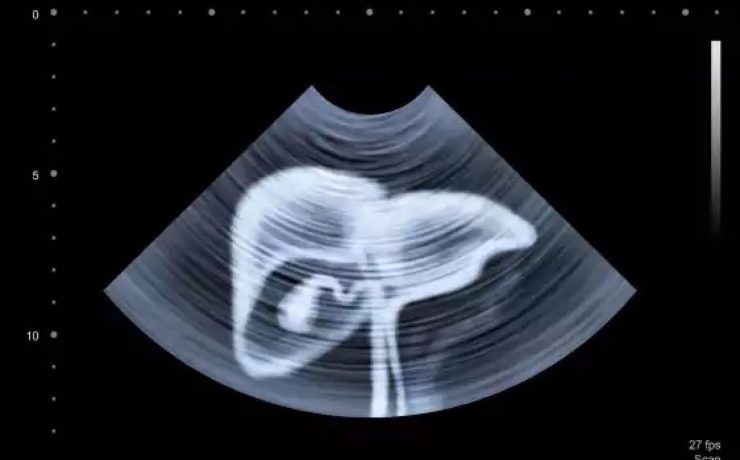

Quiste hidatídico primario de bazo

La hidatidosis es una enfermedad causada por Equinococus granulosus y que afecta principalmente a zonas endémicas donde existe disminución de la higiene, lugares con corrales o animales con problemas intestinales, alimentos donde se consumen vísceras crudos, en lugares urbanos se ha visto este tipo de patología donde abundan los perros